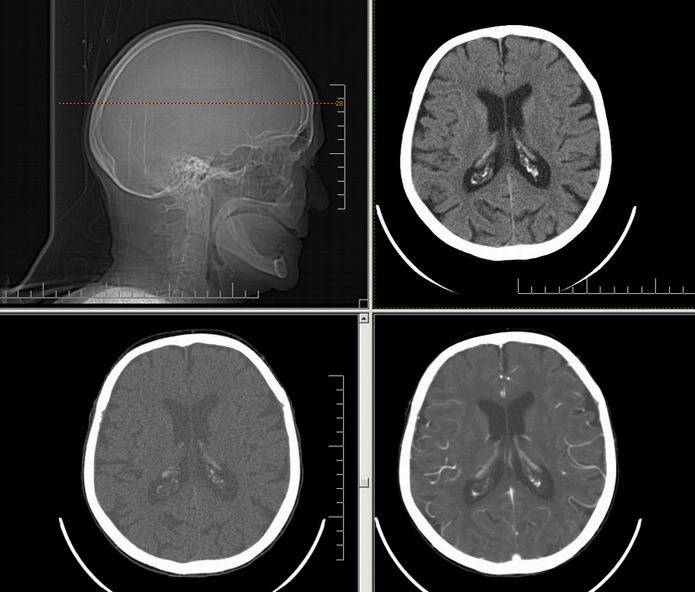

Est ce que qqun a des coupes axiales de crâne pour m'aider à réviser mon anatomie. Merci

Pour compléter tes révisions, Poupette vient de nous faire parvenir ces planches bien utiles: Planches de coupes axiales cérébrales, dans la rubrique COURS / ANATOMIE